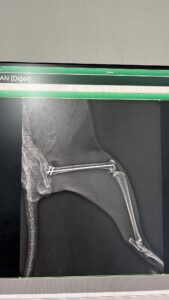

This cat, who lived in Kenan Aral’s garden, had its hind leg broken after being hit by a car and underwent surgery today at Cadde Clinic. He is currently recovering. Please support us so we can help this cat and our beloved companions in similar situations.